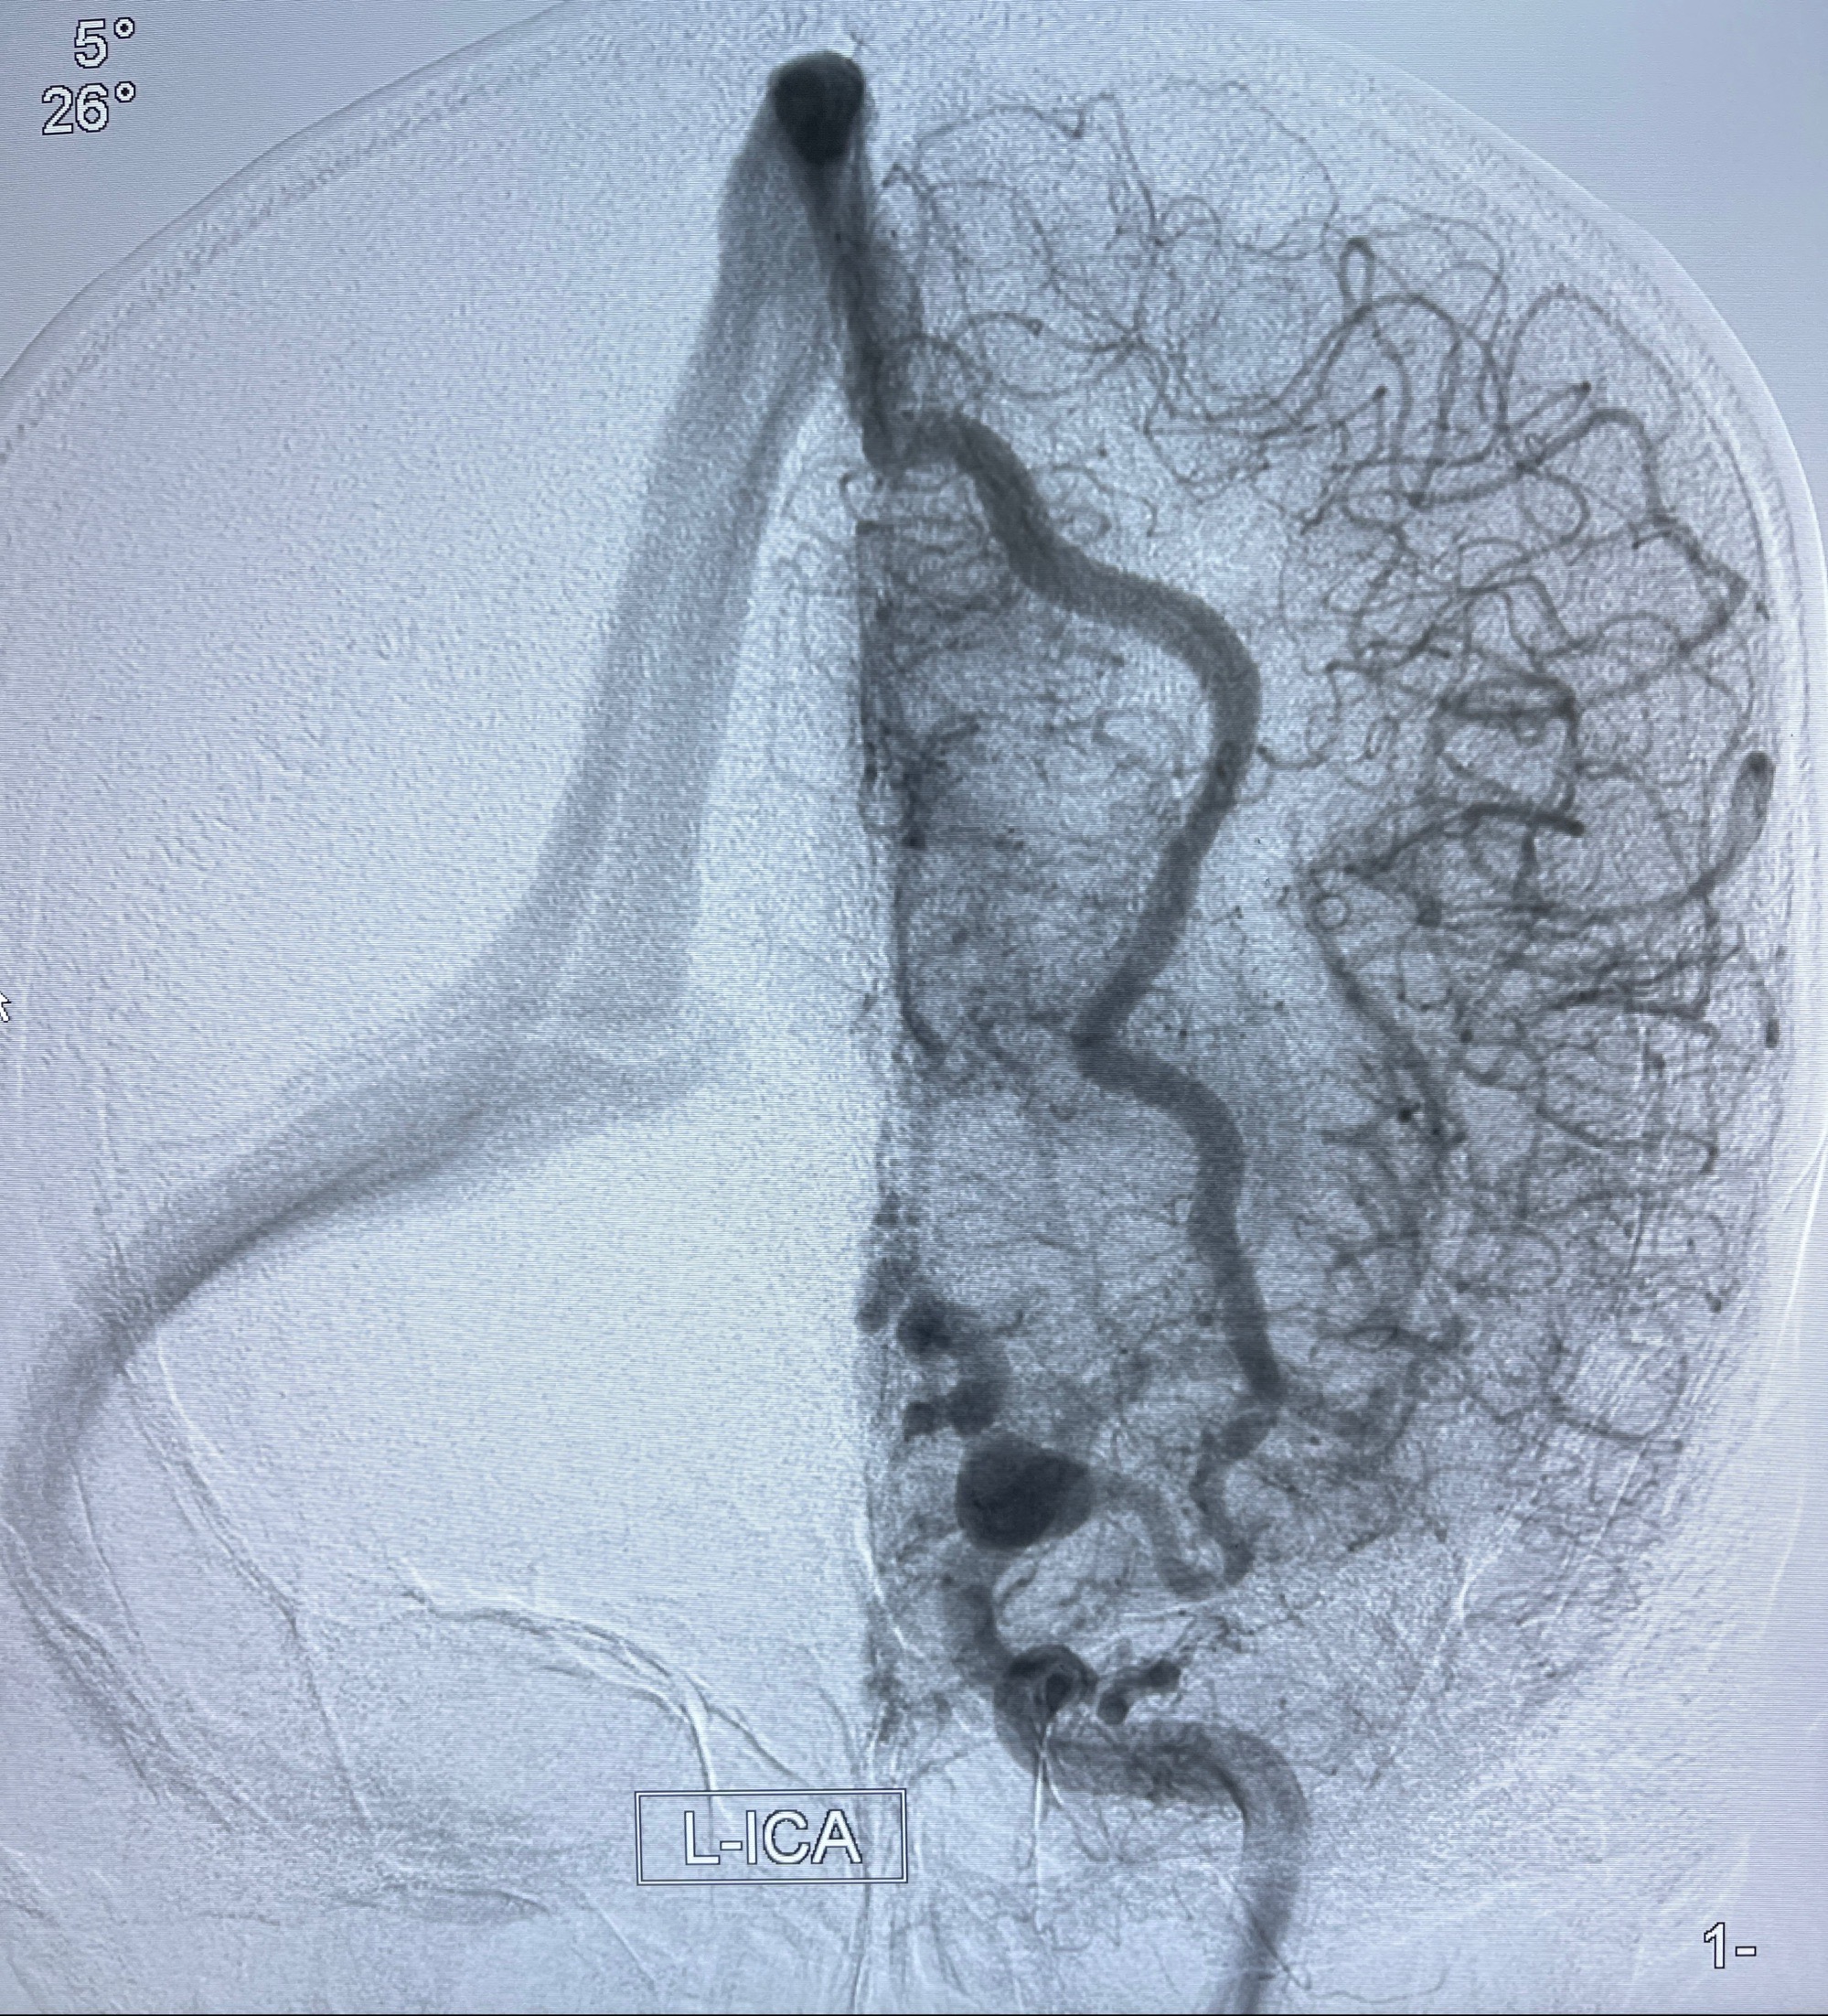

2023年8月21日]景德镇市第一人民医院脑血管造影检查,提示:主动脉弓、双侧颈总动脉、锁骨下动脉造影未见异常,左侧大脑前动脉静脉瘘。

2023-09-13全脑血管造影:前颅底硬脑膜动静脉瘘,供血动脉为双侧胼周动脉、眼动脉脑膜支,静脉向上矢状窦方向引流